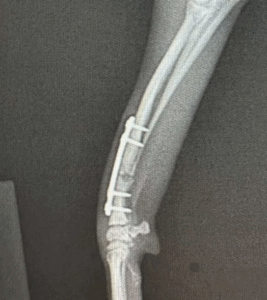

- 治療法の有効性の評価 骨片の位置やインプラントの安定性を確認し、治療計画が適切に機能しているかを評価しています。

- 治癒の進行確認 骨片の整列状態や仮骨の形成状況、インプラントの安定性を評価します。